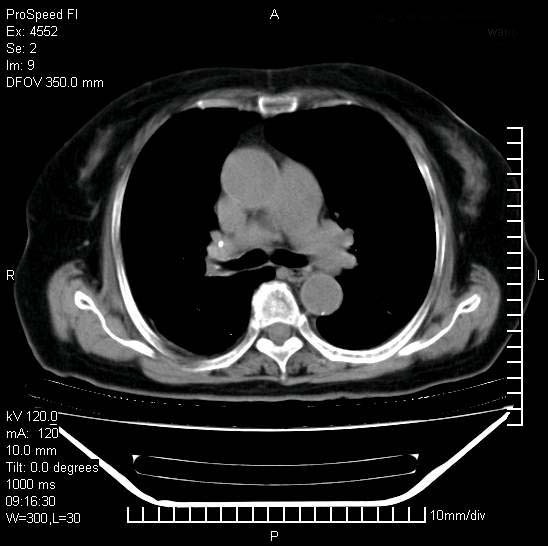

十几年前曾患肺结核,一周前突咳血约100ml,中性粒细胞稍高,诊断两上肺陈旧结核,下肺炎症,给予抗炎治疗,近几日晚上高热,39度,仍咳少量血,4天前ct及今天ct上传。

今天ct

短短几天内,病变范围明显增多扩大,以左侧明显,而且双侧出现胸水,还是考虑感染.

短短几天内,病变范围明显增多扩大,以左侧明显,而且双侧出现胸水,我更多考虑左侧中心性肺癌并并阻塞性不张及肺炎,炎症变化也太快了!

无论是肿瘤还是炎症4天的时间都发展够快的,并且还在治疗中,如果说是左肺癌那么右肺的病变不好解释,本人更加倾向于炎症,左肺舌叶支气管被痰栓或血凝块堵塞,造成阻塞性肺炎。

1)两肺结核并感染。2)不排除左肺上叶中央型肺癌并阻塞性肺炎、肺不张可能;建议行纤支镜检查。3)右肺门及纵隔淋巴结肿大。4)双侧胸腔积液。

陈旧性肺结核及左下肺不张,咯血后肺部感染,双胸腔积液,高热可能与痰液引流不畅有关。